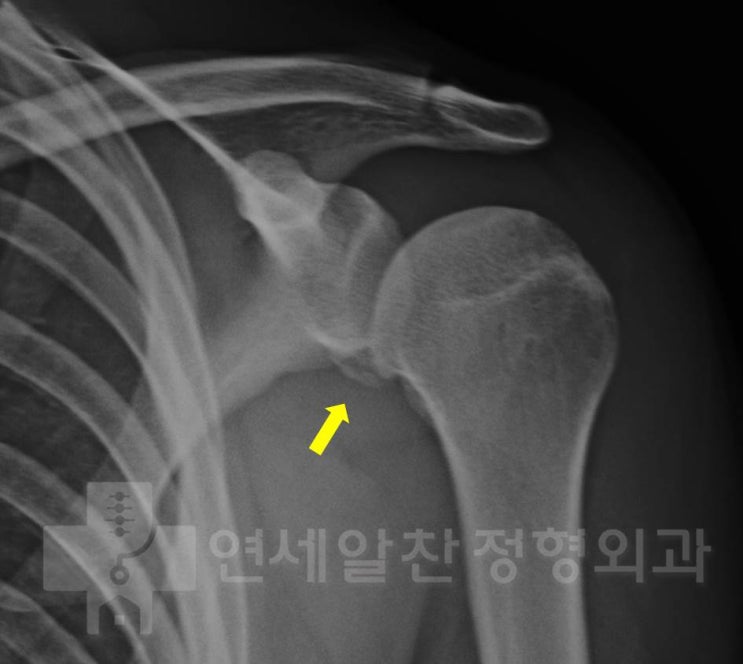

무지외반증에서 근위절골술을 이용한 교정절골술의 결과

71세 남자 환자로 좌측 발 통증을 주소로 내원하였다. 환자는 수차례의 스테로이드 주사를 맞았으며 최근 ...